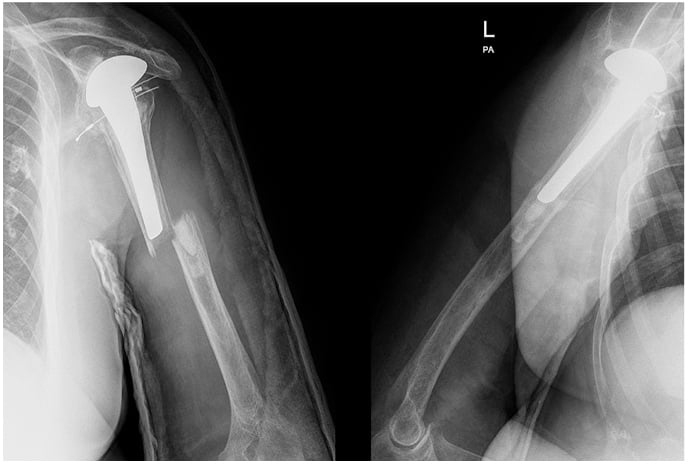

He presented 10 days after injury and was neurovascularly intact. His left shoulder had relatively poor range of motion prior to the injury, but the patient lived independently and performed all activities of daily living. X-rays demonstrated a transverse fracture through the cement mantle of a well-fixed cemented left shoulder hemiarthroplasty (Fig. 1). He was indicated for open reduction and internal fixation of the left humerus.

Figure 1: Anteroposterior and lateral images at presentation show a transverse fracture through a cemented left shoulder hemiarthroplasty performed 12 years prior.